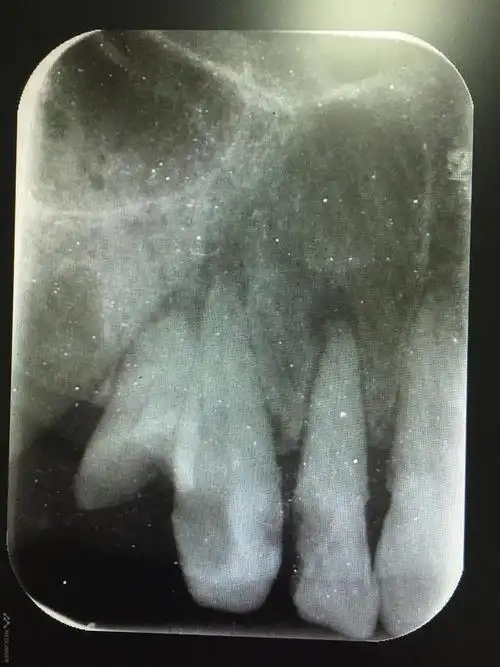

根尖炎(牙髓炎)

12牙14牙慢性根尖周炎

左上前牙根尖周炎一例

左下后牙根尖周炎一例

右下后牙隐裂导致根尖周炎